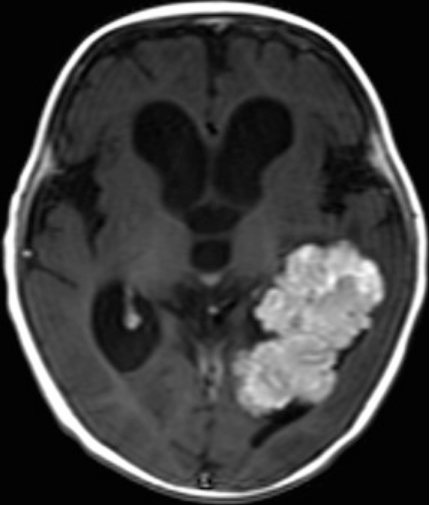

脑室肿瘤(又称脑室内肿瘤),顾名思义,是指在脑室内发现的肿瘤或病变。脑室是充满液体的结构,具有四个心室,其产生的脑脊液覆盖大脑和脊髓。脑脊液从侧心室流入三脑室,然后,这些液体通过大脑导水管(Sylvius)进入四脑室,从大脑内部流出,在大脑和脊髓周围循环,然后被吸收回血液流。因此,而产生于该区域类的肿瘤可以局部阻断血流,经常阻碍脑脊液的流动,并导致颅骨内压力的增加。由于颅压的增高,所以许多患者会感受到头痛,并且这种头痛不会消失,随着肿瘤的增大而不断加重痛觉,所以李女士多次吃药也不见效果。

关于脑室肿瘤的治疗,James T.Rutka教授表示,脑室肿瘤一般治疗优选手术,但由于脑室肿瘤的位置、大小、与脑积水的关系以及周围的功能解剖所带来的挑战,脑室肿瘤的治疗存在争议。MRI是术前评估的优选方法,需要考虑的重要因素包括肿瘤的大小、肿瘤血管的供应和引流、脑积水和周围的神经结构。较后,在难以获得脑室肿瘤的情况下,可以利用脑室内窥镜进行诊断。这种微创手术对较小的病变或需要活检病理诊断的放射敏感性肿瘤是有吸引力的,并且是成功的。

关于脑室肿瘤的手术治疗,James T.Rutka教授认为,理想的手术应达到足够的暴露以切除更多的肿瘤,同时快速识别供血血管,尽量较小程度使大脑收缩和功能皮层损伤达到较小。手术时,选择在外科医生和病变之间较直接的轨迹,来进行手术通常是较合适的,但是选择是可变的,并且取决于手术医生的经验。脑室内肿瘤位置、脑积水、半球形优势、肿瘤大小、肿瘤血管供应、组织病理学特征均为重要因素。立体定向指导系统有助于选择适合的方法,以实现顺利、的肿瘤切除。对于脑室肿瘤的手术入路,James T.Rutka教授表示,历史上,神经外科医生常使用经皮层的方法进入侧脑室。近年来,经胼胝体-大脑半球间入路因可直接进入脑室而不损伤皮质脑组织而更常被使用。对于三和后脑室肿瘤,经皮质颞叶、顶叶上叶和经胼胝体-半球间入路是常见的。